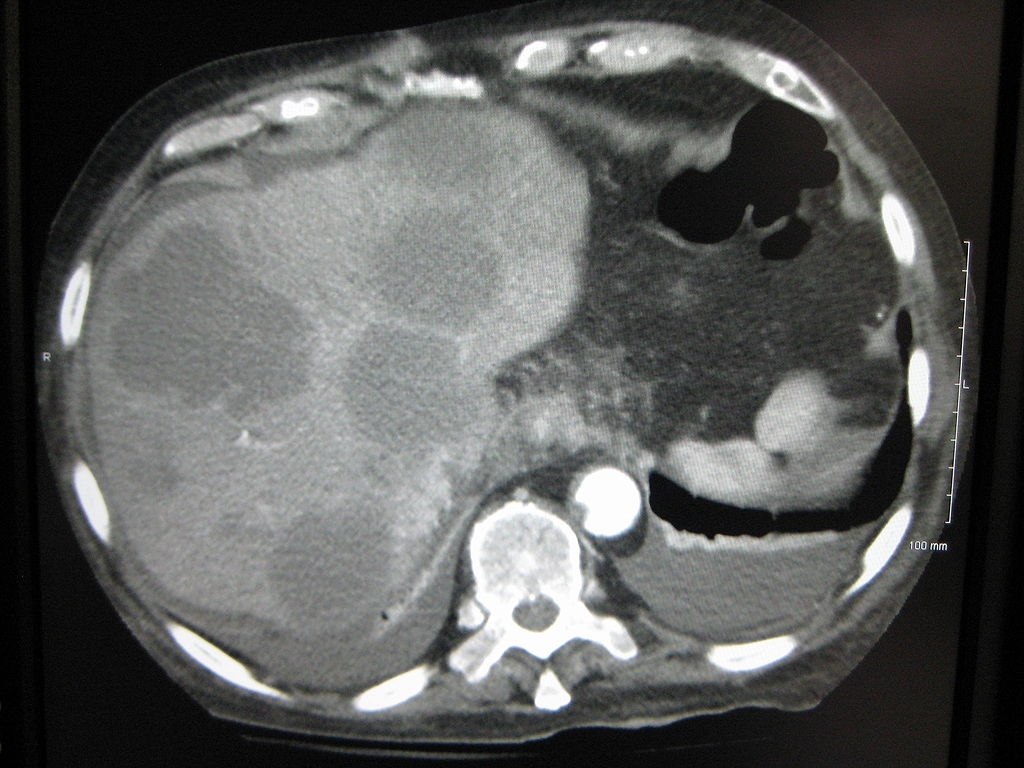

| Axial CT of the abdomen showing multiple liver metastases. Image courtesy of James Heilman, MD / Wikimedia Commons / CC-BY-SA-3.0 |